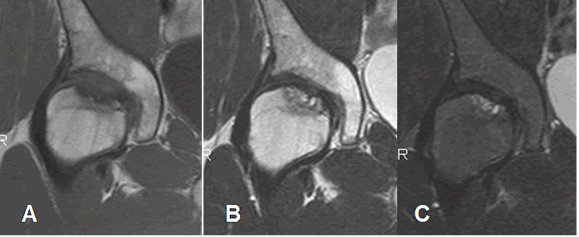

Fig 83 B. Osteonecrosis. Clase C.

A: RM coronal en T1, B: RM coronal en T2 y C: RM coronal en STIR. Zona hipointensa en T1, hiperintensa en T2 y STIR, en la parte superior de la cabeza femoral, por osteonecrosis subaguda.